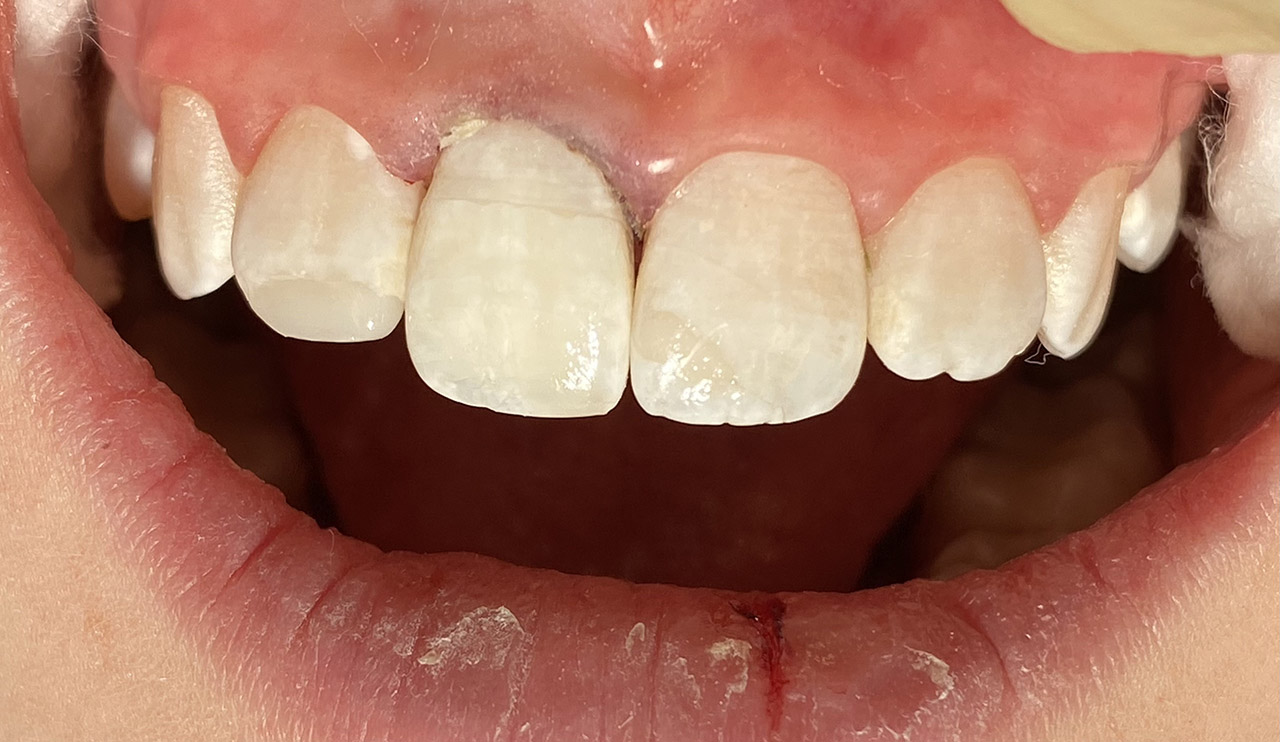

Nach Unfall mit E-Scooter unbefriedigendes Ergebnis der Erstversorgung (alio loco). Therapievorschlag: Stiftzähne?

Unsere minimalinvasive Therapie: Revision der Wurzelbehandlungen, danach internes und externes Bleaching, adhäsive Kunststoffüllungen in Schichttechnik. (Titel meiner Diplomarbeit 2003 “Die Vermeidung von Extraktion und Wurzelspitzenresektion durch zeitgemässe Endodontie in der Privatpraxis”)